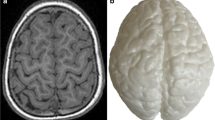

As mentioned, only 12 patients were selected for 3D printing due to limitations of printer availability and cost. Of these, 3 demonstrated the basal ganglia and thalamic (BGT) pattern with perirolandic cortical atrophy, 3 had focal cystic encephalomalacia, 3 had cortical watershed atrophy, 2 had diffuse cortical atrophy, and 1 was normal. Figures 1 and 2 show examples of the corresponding MRIs and 3D printed models.

Comparison of axial T1W MRI image (a) with vertex view (b) and side oblique view (c) of the corresponding 3D printed model. The areas depicted by the red arrows correspond to subtle localized atrophy involving the peri-rolandic region of both cerebral hemispheres, sustained from a remote prior profound hypoxic ischemic injury in an 11-year 5-month-old girl. The black arrows depict the inter-hemispheric/lentiform separation due to the atrophy. The MRI image (a) depicts one aspect of the atrophy while the 3D printed model image (c) demonstrates the extension of involvement to the inferior and lateral aspects of the left pre-central gyrus to good effect